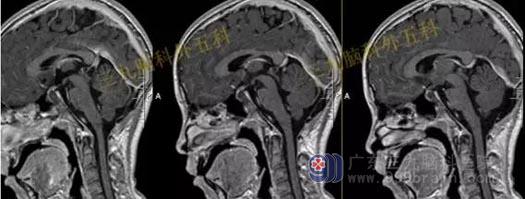

头部MR检查提示:鞍上区-桥前池见一不规则囊性病变,T1WI呈低信号,T2WI呈高信号,FLAIR呈低信号,增强扫描前缘可疑斑片状强化,病灶范围约2.9cmx3.9cmx3.1cm,视交叉受压向前上方移位,脑干、双侧颞叶内侧受压,幕上脑室系统扩大,脑池、脑沟未见增宽,中线结构居中。

手术过程:内镜下扩大经鼻蝶入路,行鞍上区颅咽管瘤切除术+颅底重建术,术中肿瘤切除,垂体及垂体柄、视神经及视交叉、双侧颈内动脉保护良好,腹部脂肪及鼻中隔粘膜瓣修补鞍底。

术后复查头部MR检查原病灶已切除。